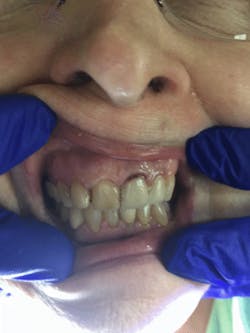

As I applied it to the facial margin of her No. 9 crown, the exposed root turned black, indicating presence of decay (figures 3 and 4). I followed up with the second solution of potassium iodide on No. 9. A creamy white precipitate formed and transformed to a clear precipitate, replacing the black stain (figure 5).

Figure 3: No. 9, prior to the Riva Star application

Figure 4: No. 9, after the application of Riva Star silver diamine fluoride

Figure 5: No. 9, after the application of Riva Star potassium iodide solution